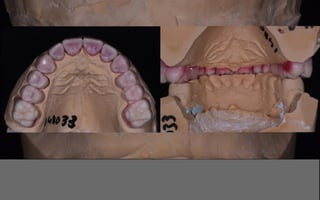

intra-oral examination/study cast:

cro = mip

possibility to open the envelope of function

functional/aesthetic wax-up in centric relation

wax-up used for a preparation guide

“minimal invasive”